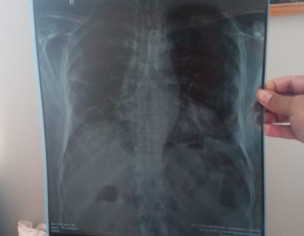

Asking for Father, Male, 65 years old, Karachi

My father has cough and chest weakness. We consulted a doctor and he suggested chest checkup. He said "it's just chest infection", we went for second opinion and the second doctor said "serious lungs infection". Please guide me, is this something serious or just chest infection? What do you suggest in this condition?

any smoking history ?

go for COVID-PCR